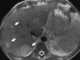

Metastatic adenocarcinoma

Adenocarcinoma (; plural adenocarcinomas or adenocarcinomata ) (AC) is a type of cancerous tumor that can occur in several parts of the body. It is defined as neoplasia of epithelial tissue that has glandular origin, glandular characteristics, or both. [Source: Wikipedia ]